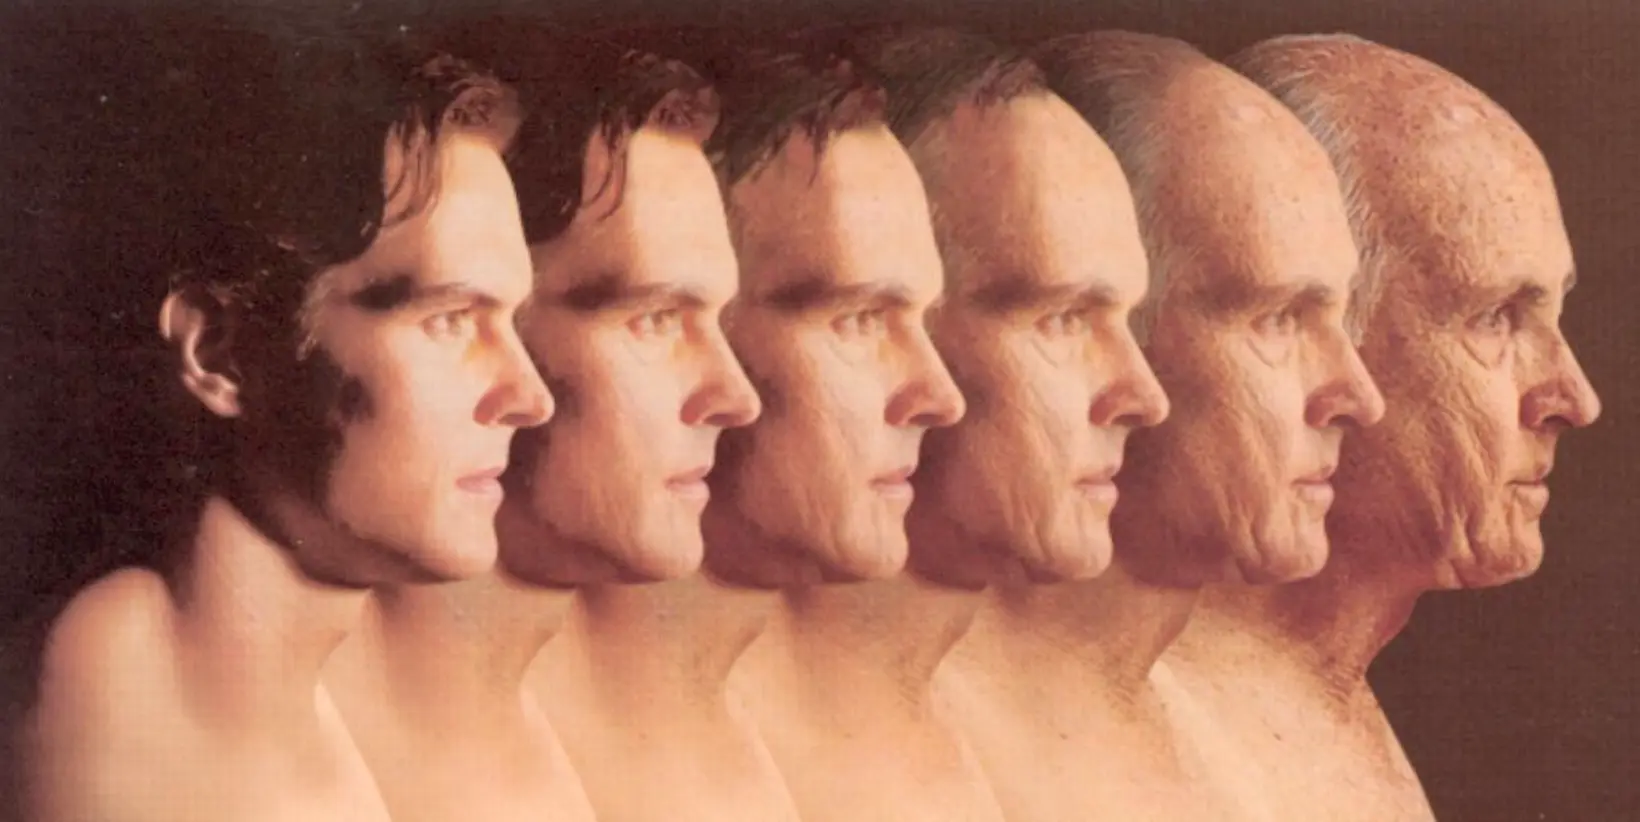

Viewing Senescence from An Evolutionary Perspective

Aging is inevitable. Although the average lifespan of humanity has dramatically increased due to developments in diets, hygiene, and medical care, death is still an unavoidable destiny.

By Yoonjin Lee & Ahhyeon Kim